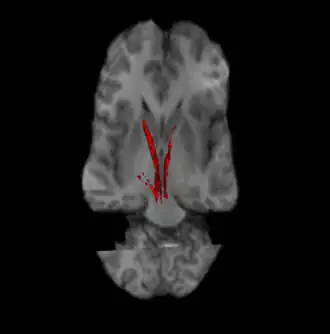

![]() Nigrostriatal pathway (Left and Right in red). | |